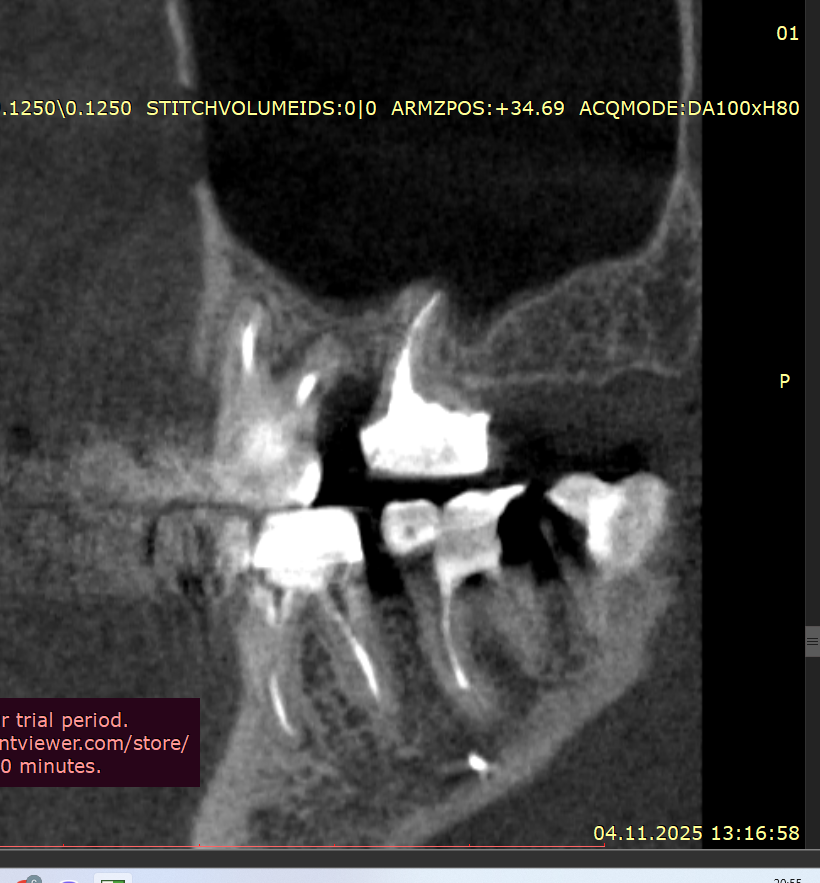

Добрый вечер Подскажите пожалуйста, вчера ел арахис, это очень редко бывает и мне такое противопоказано, и слышу один твёрдый попался немного, в момент когда накусил немного в области 4–5 зуба вверху справа, почувствовал боль, которая по сейчас сохраняется, боль чувствую именно в периодонте (к сожалению кто меня помнит с моей историей длительной я уже знаю как отличать боль по чувствительности, ту или иную), делал КЛКТ 3 недели, просто планово по поводу других зубов, посмотреть что и далее сохраняется положительная динамика после больших перенесённых периодонтитов, в вот посмотрел заодно на вот эти (открыл дайком) где вчера накусил, там нет и не было деструкции кости, зубы давно мертвые и нужно менять реставрации, зубы эти при надавливании пальцем не болят, жевать тоже не усиливается, просто ноющая периодонтальная боль извините за сленг, острой боли прям в момент накусывания арахиса тоже не было

Предполагаю что это возможно травматический периодонтит, если так, то какова тактика ?

Рентген сегодня сделал, трещины нет, но я слышал не на рентгене не на клкт часто трещины не видны, и лишь только под микроскопом